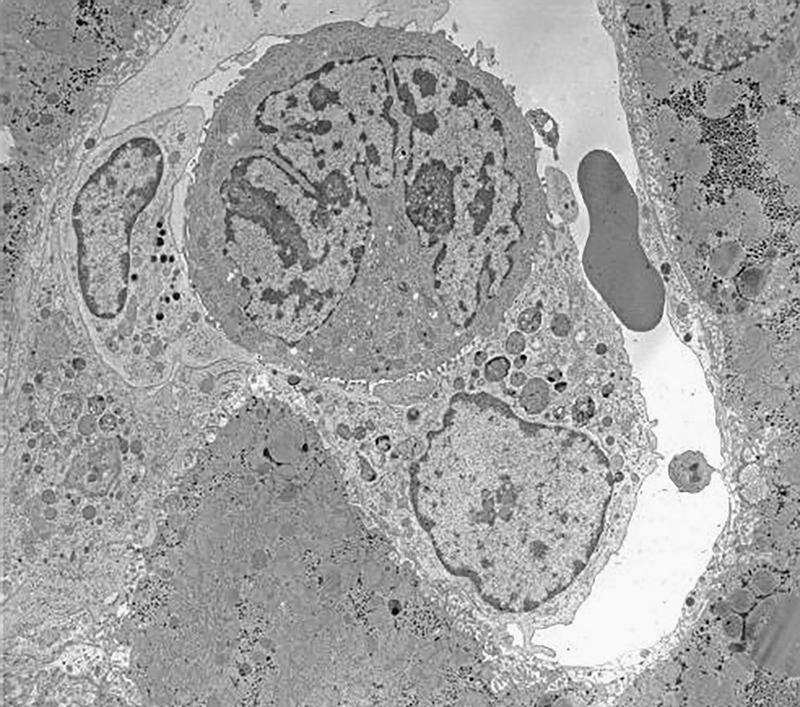

肝脏自然杀伤细胞:亚群及其在肝脏免疫中的作用。

Liver natural killer cells: subsets and roles in liver immunity.

The liver represents a frontline immune organ that is constantly exposed to a variety of gut-derived antigens as a result of its unique location and blood supply. With a predominant role in innate immunity, the liver is enriched with various innate immune cells, among which natural killer (NK) cells play important roles in host defense and in maintaining immune balance. Hepatic NK cells were first described as 'pit cells' in the rat liver in the 1970s. Recent studies of NK cells in mouse and human livers have shown that two distinct NK cell subsets, liver-resident NK cells and conventional NK (cNK) cells, are present in this organ. Here, we review liver NK cell subsets in different species, revisiting rat hepatic pit cells and highlighting recent progress related to resident NK cells in mouse and human livers, and also discuss the dual roles of NK cells in liver immunity.

摘要

肝脏是一个前沿免疫器官,由于其独特的位置和血液供应,它不断接触各种来自肠道的抗原。肝脏在固有免疫中起主要作用,富含各种固有免疫细胞,其中自然杀伤(NK)细胞在宿主防御和维持免疫平衡中发挥重要作用。肝脏NK细胞在20世纪70年代首次在大鼠肝脏中被描述为“pit细胞”。最近对小鼠和人类肝脏中NK细胞的研究表明,该器官中存在两种不同的NK细胞亚群,即肝脏驻留NK细胞和传统NK(cNK)细胞。在这里,我们回顾了不同物种中的肝脏NK细胞亚群,重新审视大鼠肝脏pit细胞,并强调与小鼠和人类肝脏中驻留NK细胞相关的最新进展,同时也讨论了NK细胞在肝脏免疫中的双重作用。